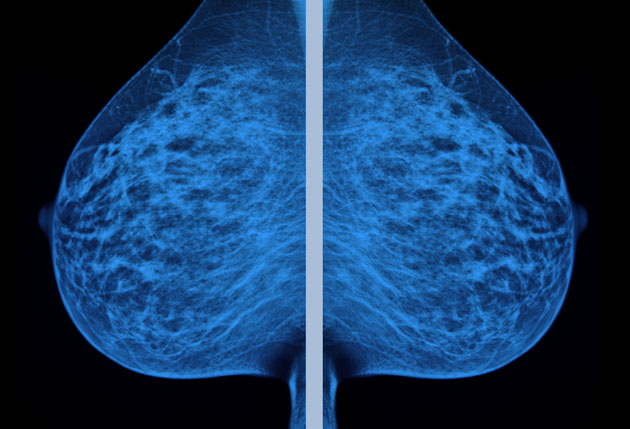

No one—not her physician or her surgeon or the pathologist or nurse or anyone else—ever took the time to explain what her mammogram and biopsy had found.

Despite what her doctor said (“It’s indicative of cancer”), the fact was that the abnormality on Taylor’s mammogram—ductal carcinoma in situ, or DCIS— is not considered a cancer by many experts, and it had only a small chance of ever progressing into an invasive cancer. The probability that it would kill her was even slimmer, about 3 percent. The thing in her breast was not a ticking time bomb, and were it not for the mammogram, she probably never would have known it was there.

If she knew then what she knows now, Therese Taylor would have refused the surgery. In fact, she would have canceled the mammogram. Taylor has come to realize that she lost her breast out of fear, not out of caution. She’s learned that her mammogram was at least three times more likely to get her diagnosed and treated for a cancer that never would have harmed her than it was to save her life. But perhaps the most infuriating thing she’s learned is that scientific evidence for the harms of mammography has been available—published in medicine’s most highly regarded journals—for decades.

What scientists know and Taylor didn’t is that mammography isn’t the infallible tool we wanted it to be. Some things that look like cancer on a mammogram (or the biopsy that comes afterward) don’t act like cancer in the body—they don’t invade and proliferate in other organs. Some of the abnormalities breast screenings find will never hurt you, but we don’t yet have the tools to distinguish the harmless ones from the deadly ones. And so these medical tests provoke doctors to categorize lots of merely suspicious cells in with the most dangerous cancers, which means that while some lives are saved, even more women end up with treatments they don’t need. Whether the chance of benefiting from a mammogram is worth the risks of having one is an individual woman’s decision, but Taylor believes her doctors owed her a truthful discussion about the potential harms before she made her choice.

Perhaps the most striking consequence of our three decades of cancer screening is the sevenfold increase in the rate of women diagnosed with the type of abnormal cell lesion found in Therese Taylor’s breast: DCIS. Sometimes called “stage zero breast cancer,” DCIS is technically a precancer. Our best guess, based on the research available, is that about 15 percent of such lesions eventually become invasive. But that research mostly looked at DCIS detected by physical exams, not mammograms—and a lump you can feel probably behaves differently (and may be more dangerous) than a lesion that’s only detectable in an X-ray, says Barnett Kramer of the National Cancer Institute. Prior to widespread mammography, most women with these noninvasive abnormalities remained blissfully unaware of them, he says.

DCIS now accounts for 20 to 30 percent of all breast cancer diagnoses, and the adoption of digital mammography is pushing those numbers even higher. “The biggest risk factor for DCIS is having a mammogram,” explains Karla Kerlikowske, a physician and epidemiologist at the University of California-San Francisco. Aggressive treatments like surgery have become alarmingly common for women diagnosed with DCIS—from 1998 to 2005, their rate of elective double mastectomy nearly tripled, and just more than 30 percent of women diagnosed with DCIS in 2012 opted for a mastectomy, even though the vast majority of them wouldn’t ever have developed breast cancer.

When celebrity chef Sandra Lee was diagnosed with DCIS via a screening mammogram earlier this year, she shared a video diary of the experience with People magazine. Lee does not have the BRCA genes that indicate a high risk for developing cancer, but she told Good Morning America‘s Robin Roberts that both her radiologist and her doctor told her, “You’re a ticking time bomb.” Lee opted for a double mastectomy. But a study published in JAMA Oncology in August of more than 100,000 women with DCIS found that their risk of dying of breast cancer was virtually identical to that of the average woman without DCIS or any signs of breast cancer.

The trend toward aggressive treatments for DCIS worried experts enough that, in 2012, the National Cancer Institute held a meeting about the problem of overdiagnosis. The researchers discussed removing the word carcinoma from the DCIS name and renaming the condition IDLE, for “indolent lesions of epithelial origin,” to discourage unnecessary treatment and help women avoid the fear that comes with the C word. The language we have matters: In one study, Shelley Hwang, the professor of surgery at Duke University, and her colleagues presented hypothetical DCIS scenarios to nearly 400 healthy women and gave them three treatment options: surgery, drug treatment, or “watchful waiting.” When the researchers told their subjects that DCIS is a “noninvasive breast cancer,” 47 percent of the women chose surgery to remove it. When DCIS was described simply as “abnormal cells,” only 31 percent did so. Our discomfort with the words “cancer” and “carcinoma” points to a larger problem: The minute a mammogram show us something scary, the equation becomes emotional, and that usually means we go down a spiral of escalating tests and diagnoses.